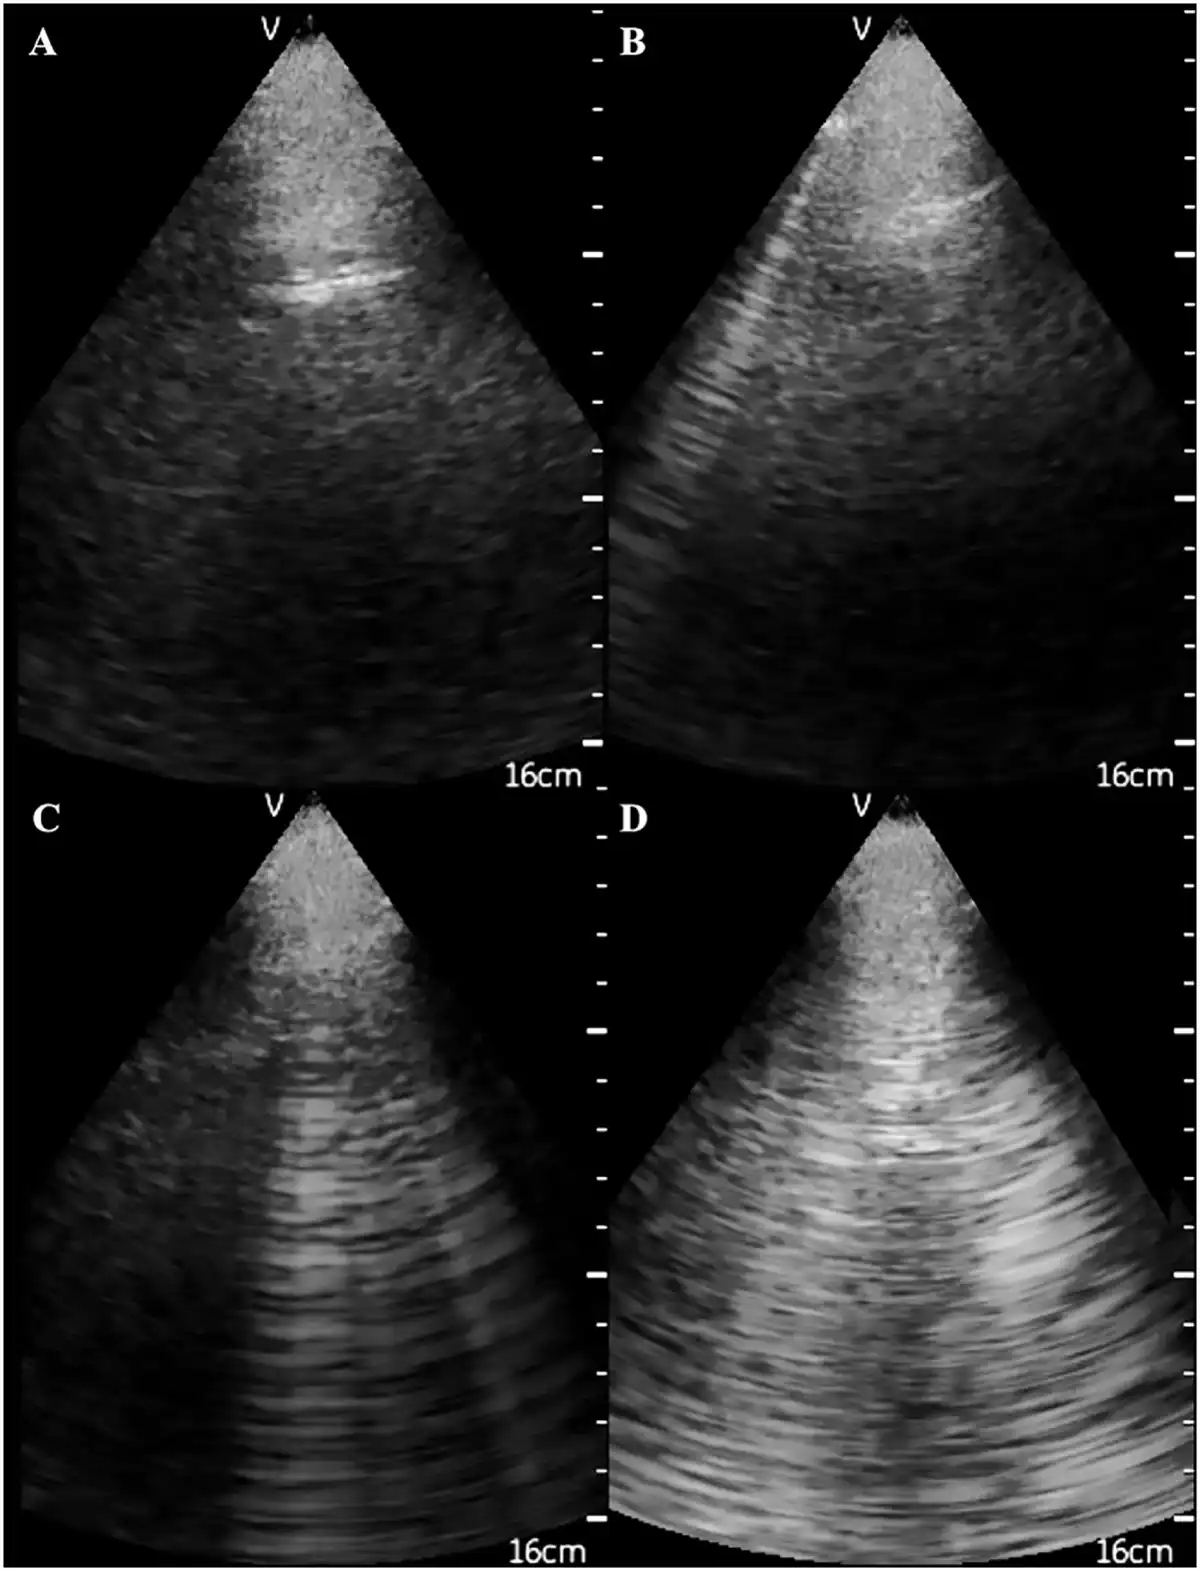

During the last decade, a novel and easy to apply ultrasound (US) technique to quantify water excess in the lungs in these patients has been developed []. Lung US takes advantage of basic principles of ultrasonography, i.e. excessive lung water in the thickened subpleural interlobular septa completely reflect the US beam, forming highly echogenic structures, the US-B lines [], which are hyperechoic reverberation artefacts between the subpleural interlobular septa and the overlying pleura (Figure 2) []. In a cross-sectional analysis of baseline data from the Lung water by UltraSound guided Treatment to prevent death and cardiovascular complications in high risk end-stage renal disease patients with cardiomyopathy (LUST) study, lung US was superior to clinical criteria in detecting and monitoring volume excess in haemodialysis patients []. The feasibility and the validation of this technique in HD patients were examined in a study including 75 HD patients []. In this study, the number of US-B lines was reproducible and had small interoperator variability. Of note, lung water as estimated by this technique modestly correlated with LV mass (r = 0.28, P = 0.01), diastolic dysfunction and LV filling pressures [early transmitral diastolic velocity (E): r = 0.31, P = 0.008; early transmitral diastolic velocities ratio (E:e‵): r = 0.48, P < 0.001], but was only weakly associated with the hydration status as measured by bioimpedance analysis []. Previous ultrasonographic techniques include measurement of the IVC diameter and collapsibility []. Measurement of IVC diameter, relative plasma volume and bioimpedance analysis during a dry weight reduction protocol guided by clinical criteria has been examined in a pilot study in 16 incident HD patients []. In this study, all methods, except bioimpedance, were overtly inadequate for capturing meaningful volume changes induced by a dry weight reduction intervention []. Recently an automated method to evaluate IVC diameter has been developed, but this device has not yet been tested in dialysis patients []. Although the inferior vena cava reflects central venous pressure, it is a poor marker of hydration status because it may be affected by respiration, right heart function and by intrathoracic or abdominal pressure changes [].

FIGURE 2

Ultrasonographic appearance of (A) normal lungs and the presence of (B) 1, (C) 4 and (D) 10 US B-lines.